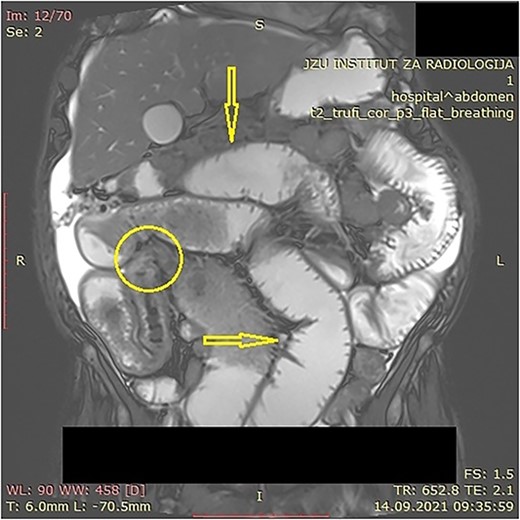

The patient was initially treated with monthly intramuscular doses of 20 mg of octreotide LAR (long-acting somatostatin analog) over a period of 5 months. During this period, the patient subsequently developed gradual partial small bowel obstruction, manifested with episodes of cramp abdominal pain and difficulties in bowel movement. Abdominal computerized tomography (CT) scan and MR imaging enterography were indicated. CT scan confirmed the presence of liver metastases and thickened small bowel wall with no confirmation of primary tumor existence (Fig. 1). MR enterography revealed small bowel distension with visible zone of transition in the right hemi abdomen (ileum) with restriction of diffusion (low signaling of apparent diffusion coefficient map) with surrounding desmoplastic reaction and visible irregular tumor with measured dimensions of 24 × 18 mm (Fig. 2).

MR enterography with dilated small bowel loops (arrows) and visible zone of transition with visual tumor in the ileum (encircled).